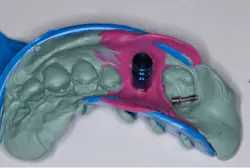

By Anthony J. Reganato, DDS, MS Implant dentistry is an exciting field that has evolved over the last 40 years or so through biological innovation. We have seen many different types of implant surface preparations that facilitate osseointegration and primary stability, and I am sure there will be further advancements in this area. We have learned of the many ways to restore single- and multiple-unit implants with different restorative configurations, various dental implant prostheses, and several loading protocols. However, only about 20% of the clinicians out there place and restore 80% of the implants. Why is this? Implant dentistry may appear to be complicated and confusing to the novice clinician ... but it doesn’t have to be.While I was a periodontal resident down in Birmingham, Ala., I was introduced to the BioHorizons® implant system, among others. There are many dental implant systems on the market, all of which have different surgical and restorative characteristics that make them appealing. However, sometimes a particular system just rubs you the right way, and that’s what happened to me as I used this particular implant system. The surgical drilling sequence was straightforward, the surgical kit was laid out nicely, but most of all, the implant system itself was simple ... and that was mainly attributable to the 3inOne BioHorizons abutment.This abutment is the actual carrier situated on the top of the dental implant that is used for surgical placement, but there are a few more uses for this abutment that make this implant so attractive for routine use when an implant restoration is planned, especially for the novice clinician who is interested in placing implants or for those docs who want a simpler way of restoring implants. Let’s discuss further the various uses of this versatile abutment.The first use of the BioHorizons 3inOne abutment is its role as the actual implant carrier, used for seating the implant into bone. I tend to find that implant systems with carriers allow for better visualization of angulation and positioning during insertion. The emergence of the carrier out of the implant is predictive of final abutment positioning, particularly when stock abutments are used. If the abutment carrier is in the appropriate restorative position, likely the use of stock abutments will follow suit.1. Implant carrier

The second use of the BioHorizons 3inOne abutment is its use as a temporary abutment. Provisionalization of an implant is in high demand by our patient populations. When the right situations present themselves, use of the 3inOne abutment may facilitate temporization of a case and eliminate the need for ill-fitting flippers or unesthetic Essix retainers. 2. Temporary abutment

The BioHorizons 3inOne abutment may also be used as the impression coping for the case. When combined with a ball-top screw that extends the height of the abutment and creates better impression accuracy, this versatile abutment may be used to obtain a more definitive impression using a closed-tray approach. Once taken and removed from the mouth, connecting these components to an implant analog allows for suitable stone model fabrication in lieu of making the final restoration.3. Impression coping

And finally, the BioHorizons 3inOne abutment can be used as the final prosthetic abutment in the case. Although most implant systems have a diverse selection of stock abutments, the simplicity of this system lends itself to the refinement of the 3inOne abutment, in order to account for proper angulation and path of prosthesis insertion. Whether one prepares this abutment chairside or submits it to the lab for modification, this abutment represents an alternative means to completing your case and expands your implant restorative armamentarium when deciding what prosthetic components should be used on a particular case.4. Final prosthetic abutment